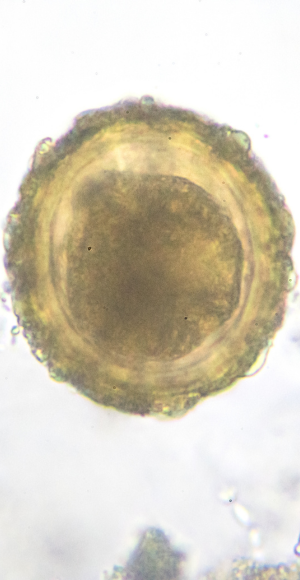

To ensure the highest level of safety, anonymous donor sperm is quarantined for at least one year, or until all follow-up tests confirm that the donor is negative for infectious diseases or health concerns.

Additionally, the quality of the donor’s sperm is thoroughly evaluated, a process that can take several months.

In fact, some sperm banks continue to test and monitor the samples for up to six months to rule out severe disorders before they are approved for use.